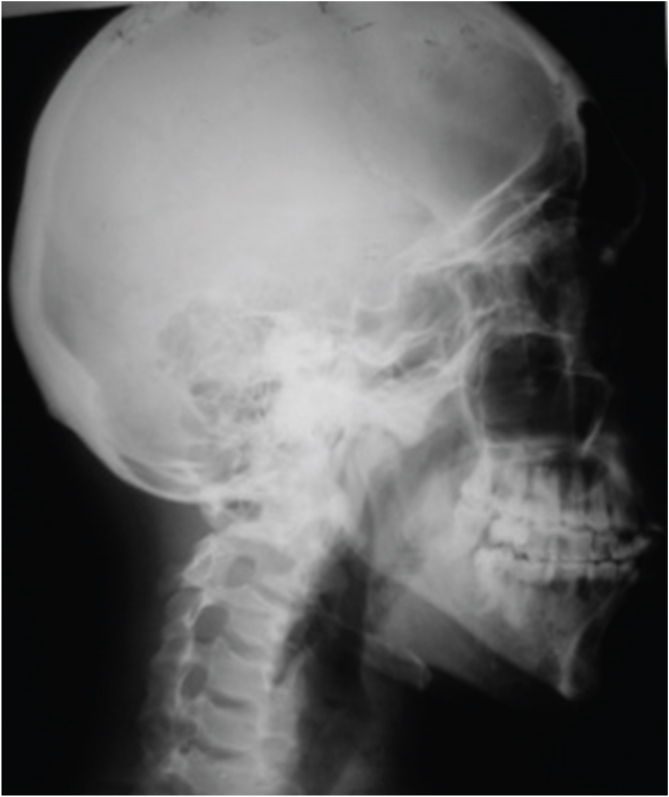

In [Table/Fig-8] intraoral periapical radiograph showing cervical resorption in relation to 33, 34, resorption in both cervical and apical region in relation to 35, 36. In [Table/Fig-9] intraoral periapical radiograph showing cervical and apical resorption in relation to 24, 25 and apical resorption in relation to 26. In [Table/Fig-10] intraoral periapical radiograph showing cervical and apical resorption in relation to 35, 36 and apical resorption in relation to 37. In [Table/Fig-11] intraoral periapical radiograph showing cervical and apical resorption in relation to 46, 47 and 48. In [Table/Fig-12] intraoral periapical radiograph showing cervical resorption in relation to 43, 44 and 45. [Table/Fig-13] Orthopantomograph. In [Table/Fig-14] lateral view of skull showing no osteogenic changes. In [Table/Fig-15] histological examination of extracted mobile teeth showing striae of Retzius, dentinal tubules and interglobular dentin with an area resembling dead tract. Correlating the history, clinical findings supported by radiographic appearance, diagnosis of Multiple Idiopathic external root resorption was made.

Lateral view of skull showing no osteogenic changes